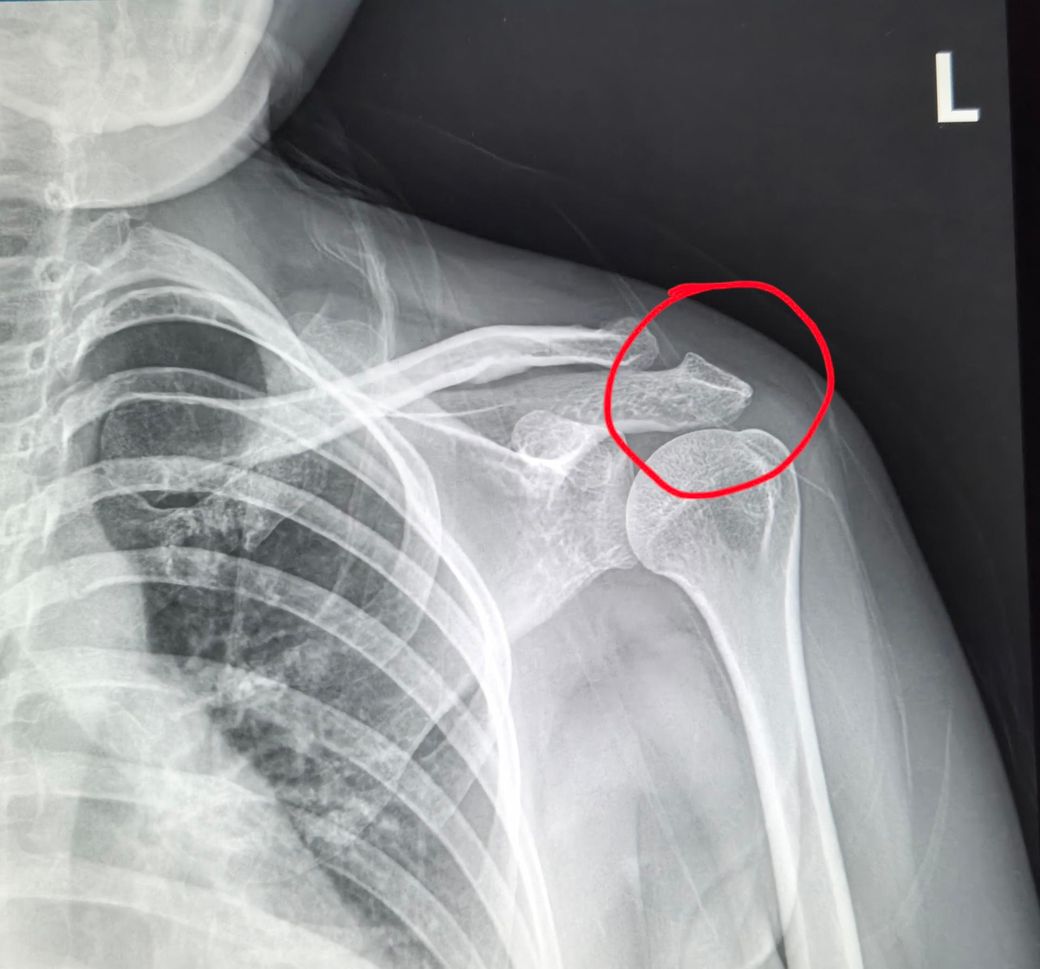

저는 2024년도에 넘어지면서 어께쪽 쇄골인가?다쳤거든요 왼쪽어께 어디뼈인지 모르겠지만 그때엑스레이찍고 약받아 먹었거든요 그때는 단순 타박상이래요. 그래서 종합병원에 다른방 선생님으로 바꿔서 2024년도에 진료를 봤어요.그때도 잘은안보이지만 뭔가 뼈에서 이상하데요.그러고 약받아먹고 말았죠.2025년도에 어께 아파서 다시가니깐 그예기를 의사가 하시더라구요. 어께쪽 뼈가 골절됬다가 붙었다고 전 이해가 안가더라구요.골절됬다가 붙을수도 있나요?

아파서요~다른병원갈지 다니는병원갈지 고민이예요.동그라미친 사진 봐주세요 붙읃거는 맞죠?미세골절일까요?

사진만 놓고 보면 동그라미 부위 쇄골끝부분이나 견봉 쪽에 뼈가 울퉁불퉁하게 튀어나온 골유합 흔적(뼈가 붙으면서 생기는 덩어리) 같은 모양이 보이긴 합니다. 그래서 담당의가 말한 것처럼 예전에 금이나 작은 골절이 있었고, 그게 붙으면서 모양이 변했을 가능성은 충분히 있습니다. 그리고 질문하신 것처럼 골절이었는데도 타박상으로 나오는 경우가 실제로 있어요. 특히 처음 다쳤을때 골절선이 아주 미세하거나 촬영각도가 애매하면 엑스레이에서 잘 안보일 수 있습니다. 결론적으로 붙은건 맞을 가능성이 높지만, 지금처럼 운동시 통증이 계속된다면 정형외과에서 어깨진료를 다시보는게 맞고, 가능하면 어깨 초음파나 MRI로 힘줄/관절 상태를 확인하는게 가장 정확합니다. 당분간은 통증 유발 동작(특히 오버헤드/무거운 프레스)은 줄이고, 재활위주로 조절하는게 안전합니다. 빠른쾌유를 빕니다!

• X-ray에서 보이는 부위는 견봉 아래 공간이 좁아진 소견으로, 견갑 전방경사·하방회전 영향 가능성이 큽니다.